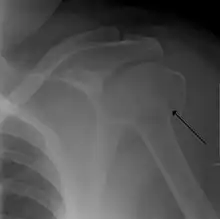

A fracture of the greater tuberosity as seen on AP X ray -

A fracture of the greater tuberosity of the humerus -